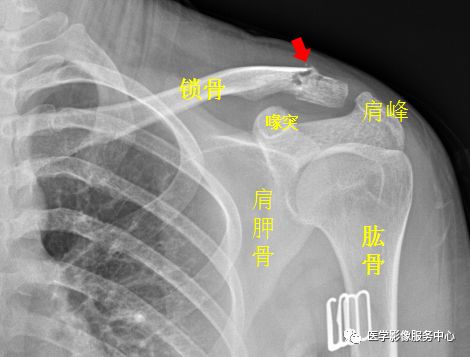

肩关节

图片

右侧肱骨大结节骨皮质欠光整,见弧形透亮线。右侧肱骨大结节骨折。

左侧锁骨肩峰端见不规则透亮线,骨折处稍移位。左侧锁骨骨折。